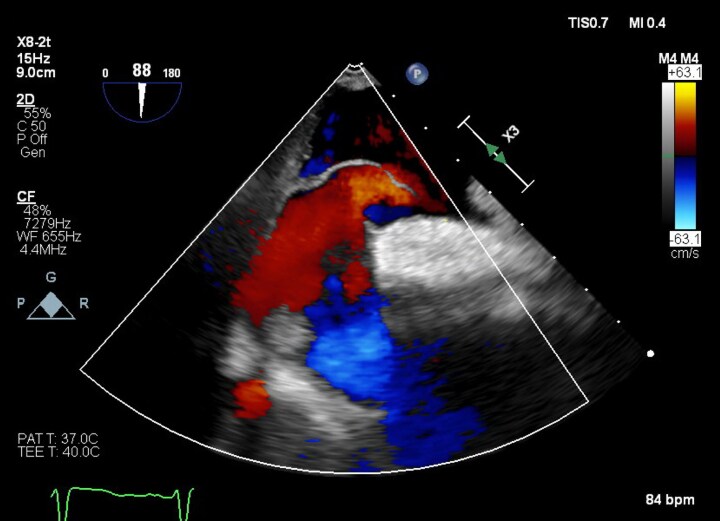

Case summary: A 77-year-old patient with severe aortic stenosis was referred for TAVI at our institution. On transthoracic echocardiography, dilatation of the ascending aorta (40 mm) and a mobile atrial septal aneurysm (ASA) were noted. Transcatheter aortic valve implantation was complicated by annular rupture and aortic intramural haematoma (IMH), managed conservatively. Three weeks after discharge, the patient re-presented with cholecystitis and underwent cholecystectomy. Post-operatively, marked hypoxaemia was noted during orthostasis. Transthoracic echocardiography showed the ASA bulging into the left atrium, with a strongly positive saline contrast study while upright. A PFO was identified on transoesophageal echocardiography and successfully percutaneously closed, with hypoxaemia resolving.